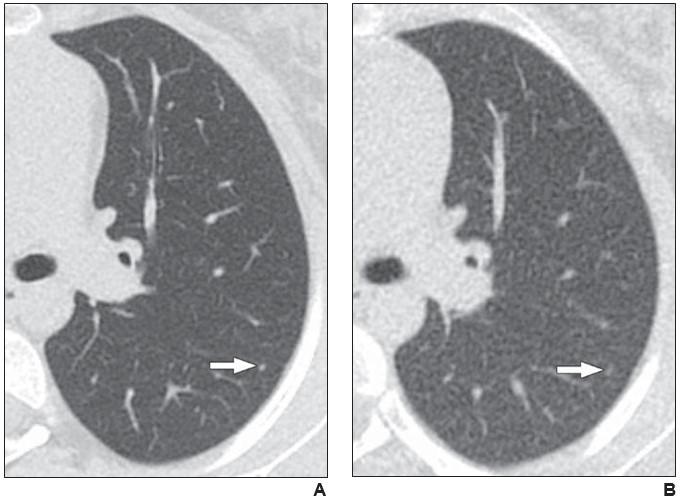

Axial reformatted clinical (1.083 mSv) and reduced dose (0.318 mSv) CT images from a 17-year-old girl with osteosarcoma. A 2 mm left lower lobe nodule is clearly visible in the left lower lobe on the clinical CT image (arrow in A). The same nodule is vaguely apparent on the reduced-dose CT image (arrow in B), classified as present but poorly visible.